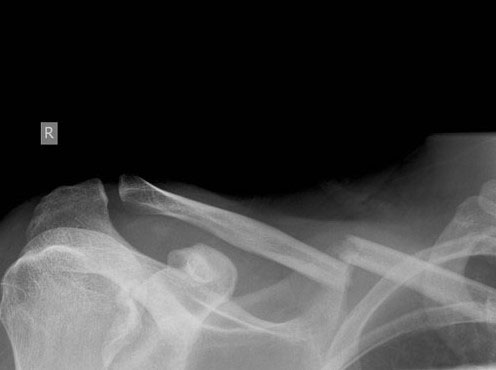

What do clavicle fractures look like on X-ray?

Below are examples of typical fractures that benefit from surgery.

Click an image to enlarge